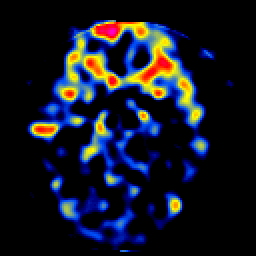

SPECT TL Study #5 -- Slice #23

[Home][Help][Clinical][Tour 1][Tour 2][Tour 3] Slice 23